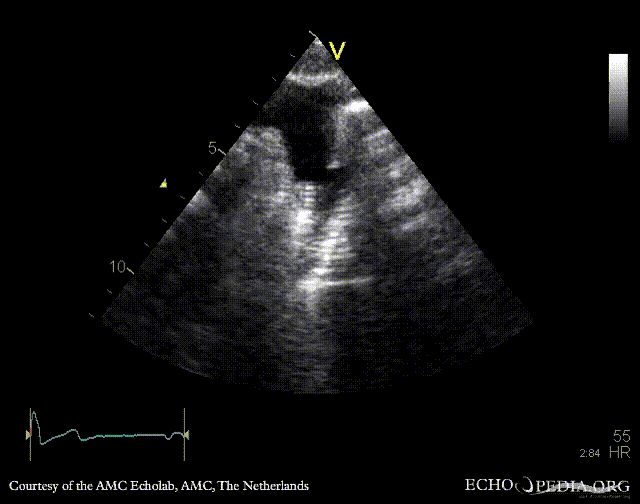

Suprasternal view: stent in aorta descendends, status after correction of coarctatio aortae Suprasternal view with color doppler